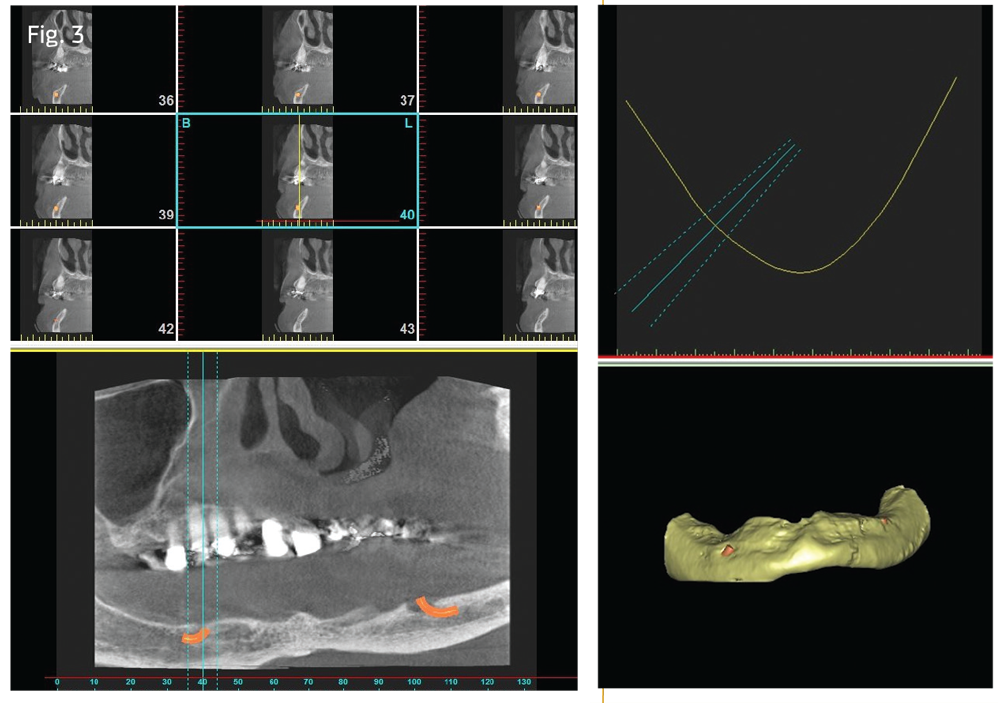

The patient left with a removable anterior denture segment. "This is the first time in years I have seen her with lower teeth," her husband said. They were both ecstatic. PVS impressions and bite registration were made to have a full-arch resin roundhouse mandibular appliance made, to be made by the Shatkin First dental lab. I asked the lab to provide room for additional implants that would be placed at the delivery visit (Fig. 5).

Visit #2: The patient arrived excited to receive her lower teeth. The temporary appliance offered improved aesthetics, but the patient still was not able to eat as she desired. After anesthetizing and administering sedation medications to her, as described for the first visit, I removed the temporary denture and placed three additional Shatkin First mini-dental implants, 2 by 10mm. This gave the patient a total of seven implants to stabilize the lower appliance. I then cemented the resin roundhouse in place (Fig. 5).

Dentaltown Magazine

Figures 5 and 6

The next step was to take impressions to prepare for the third visit. An upper PVS impression was made for the lab to fabricate an upper resin roundhouse restoration for the maxilla. (I asked the lab to remove the remaining maxillary teeth from the model when fabricating the upper appliance.) The lower opposing impression and bite registration was also taken. The extractions and implant placement would be completed at the third visit.